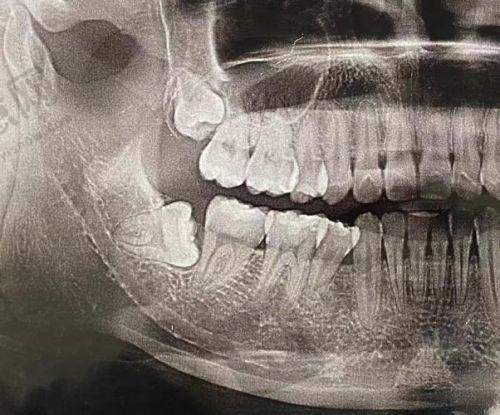

医院配备国内外化诊疗设备集群,包括德国西门子数字化口腔CT、3D导航种植系统、激光治疗设备及数字化导板制作中 心,实现种植精度达0.1mm级误差控制。在医生团队建设上,形成以廖崇元主事为核心的骨干医生梯队,团队成员均具备10年以上临床经验,其中优质职称医师占比达60%。医院采用"种植手术全程可视化"技术,通过3D导板精细定位,将传统种植手术时间缩短60%,术后并发症发生率控制在0.3%以下。

3. 数字化即刻种植:采用"口腔CT + 口内扫描 + 3D打印"三位一体技术,术前模拟种植角度与深度,术中使用导航导板精细植入,实现"拔牙 - 种植 - 戴冠"一站式完成,单颗种植体当天使用率达92%,满足患者即刻修复美观与功能需求。